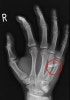

골절이나 이물확인을 위해 손의 X-ray(PA, lateral, oblique) 검사를 시행합니다.

X-ray : 인간교상(Human bite wounds)